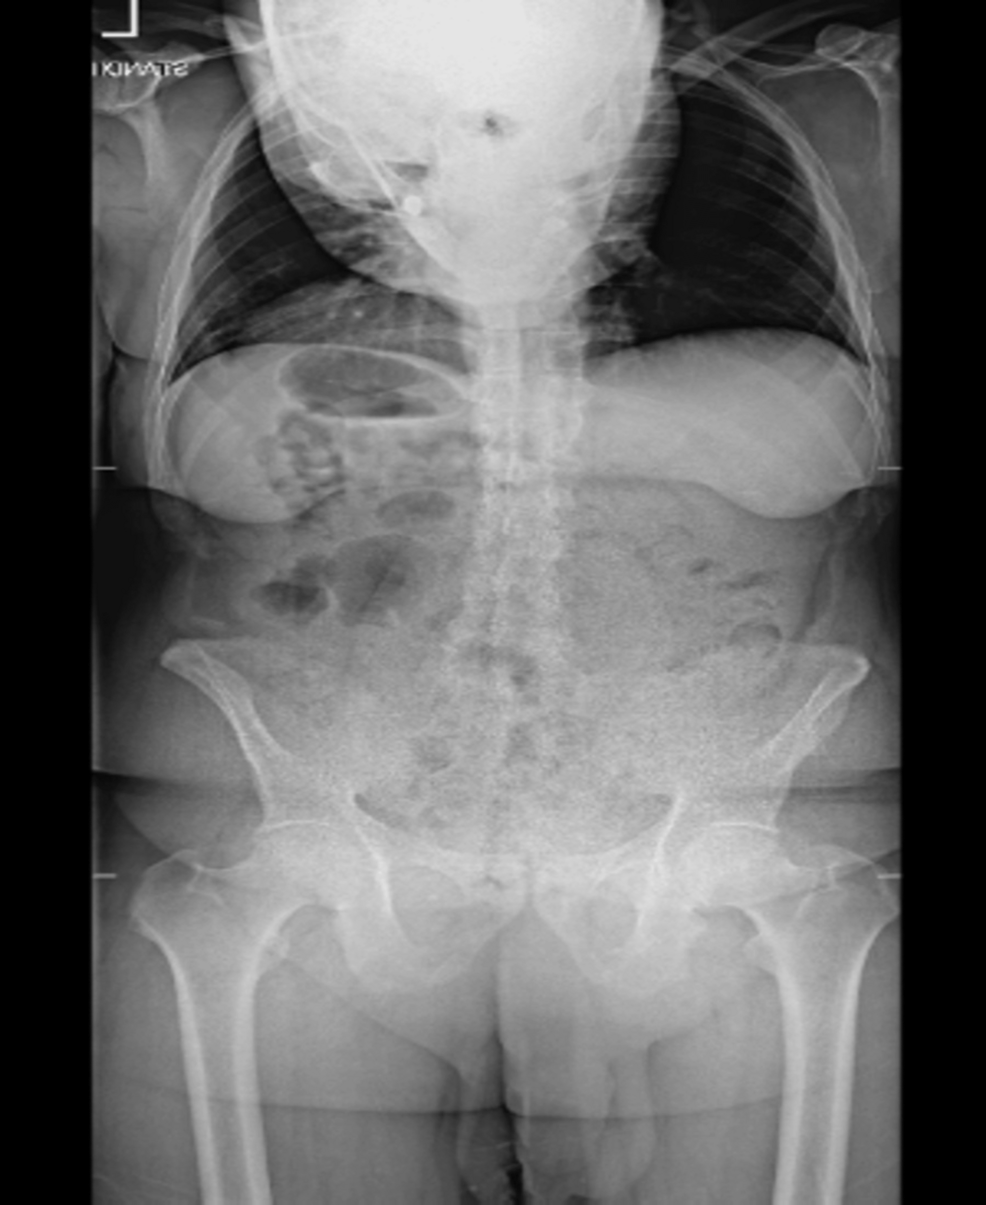

In a case study presented, the technique was successfully applied to a 54-year-old male patient with severe ankylosing spondylitis and a significant spinal deformity. Preoperative CT scans revealed a Cobb angle of 82 degrees—a measure of the spinal curvature—which was reduced to 33 degrees postoperatively. The patient reportedly experienced improved posture and reduced pain following the procedure.